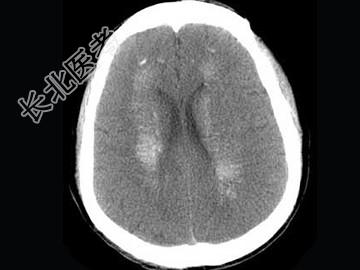

- 单项选择题男,52岁, 无明显不适,CT检查, 最可能的诊断为 ( )

A、脑血管畸形

B、结节性硬化

C、甲状旁腺功能低下

D、脑颜面血管瘤病

E、转移瘤